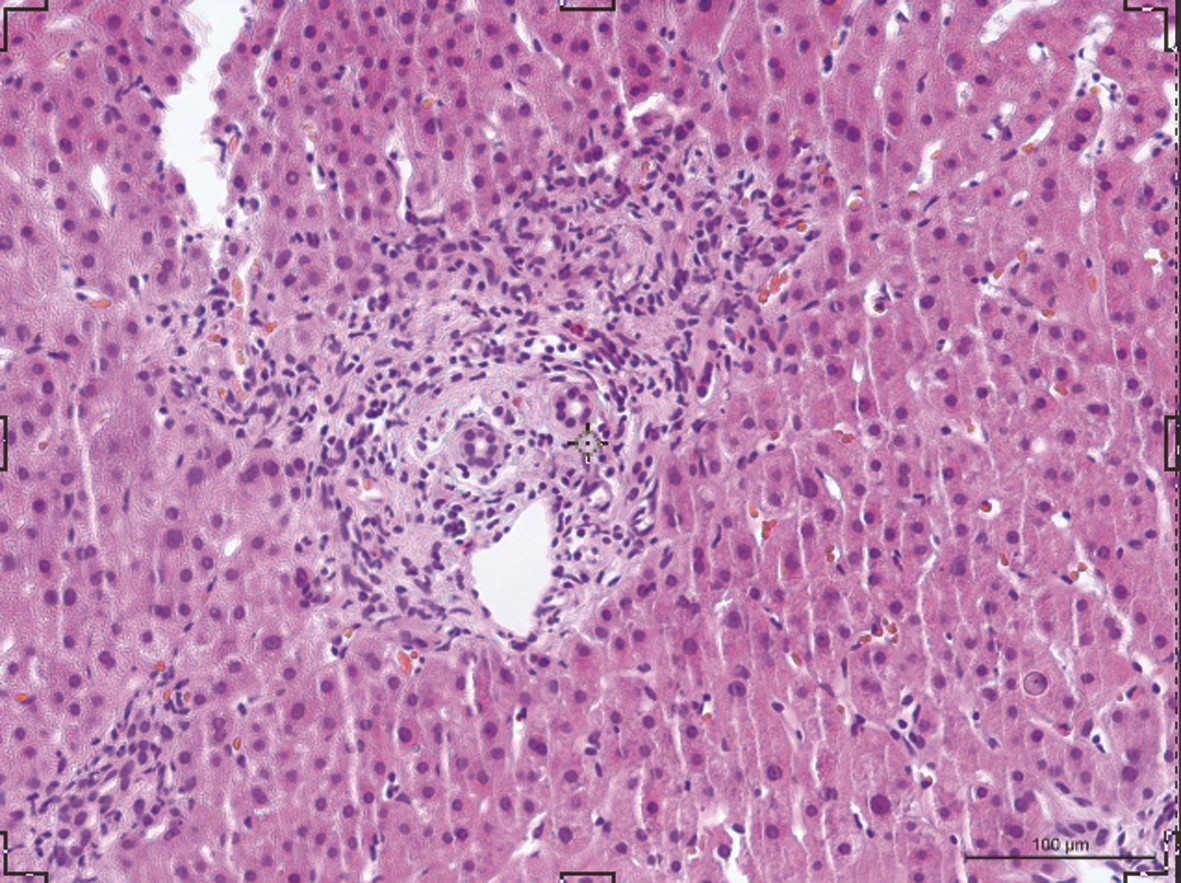

局部栓塞联合靶向免疫综合治疗肝肉瘤样癌1例报告

雷进, 张林枝, 陆荫英, 陈博文, 左石

2022, 38(4): 880-882. DOI: 10.3969/j.issn.1001-5256.2022.04.026

摘要(1328) HTML (453) PDF (3487KB)(83)

摘要: